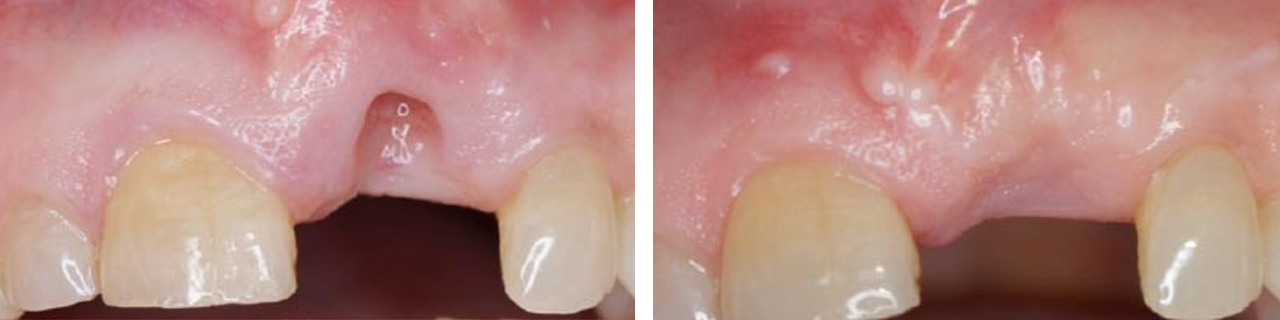

Implante

Cubrimiento gingival de implante